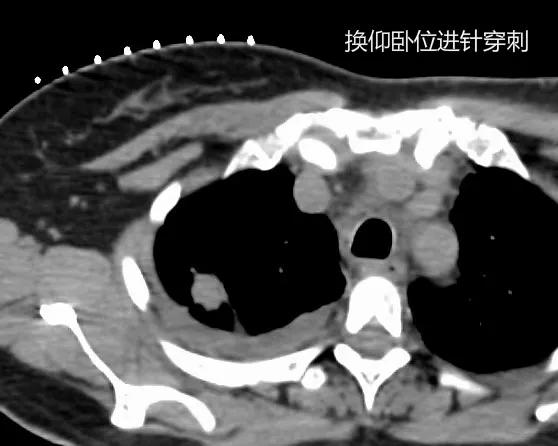

术中定位,俯卧位CT显示右上肺结节被后肋遮挡,无穿刺路径。

改用仰卧位,从前胸壁穿刺有穿刺路径